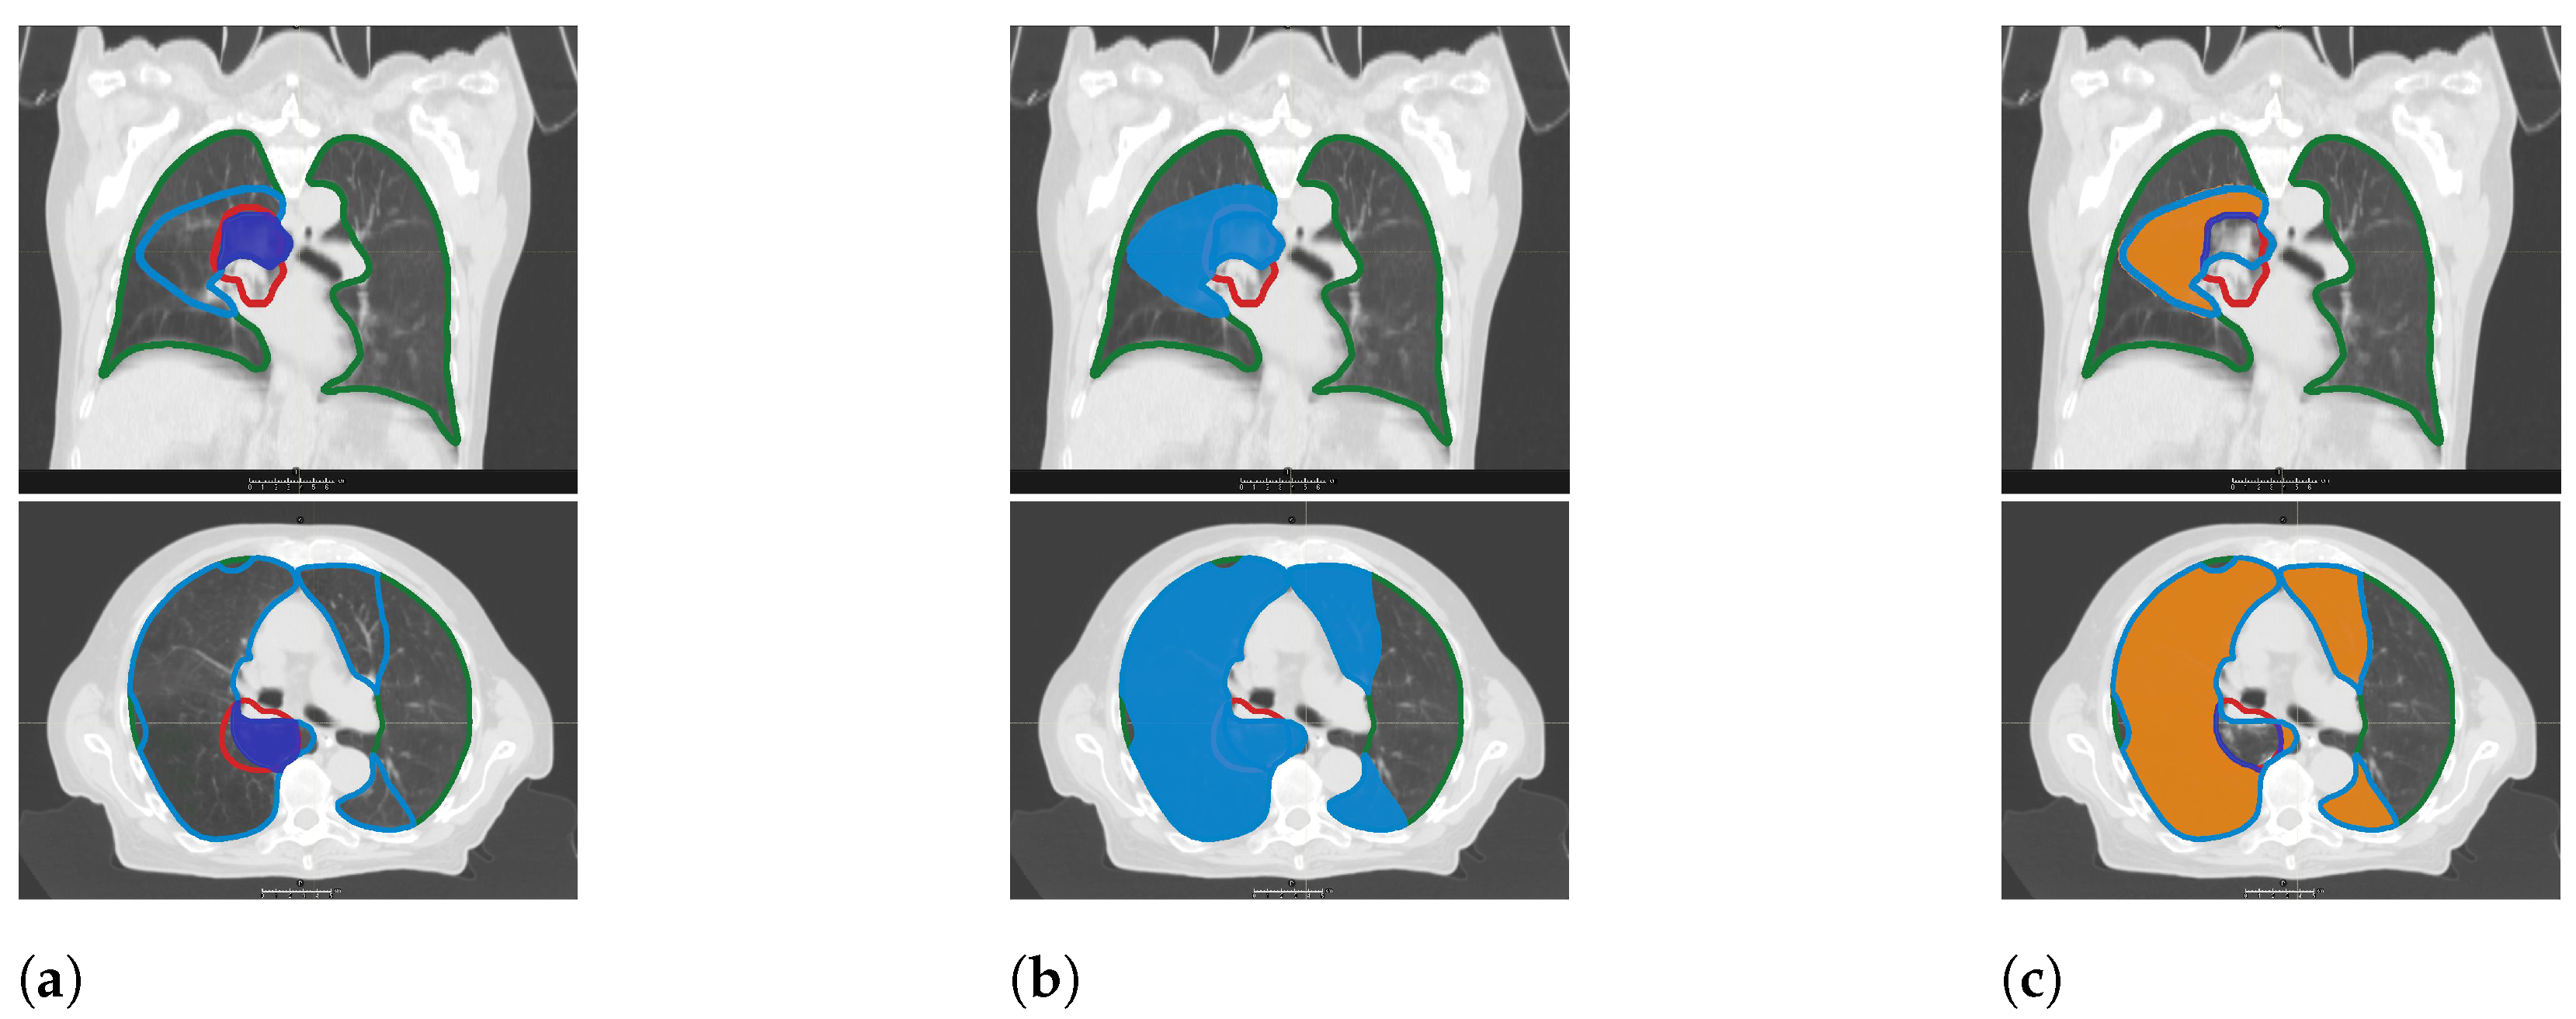

2.4. CT Morphology Changes